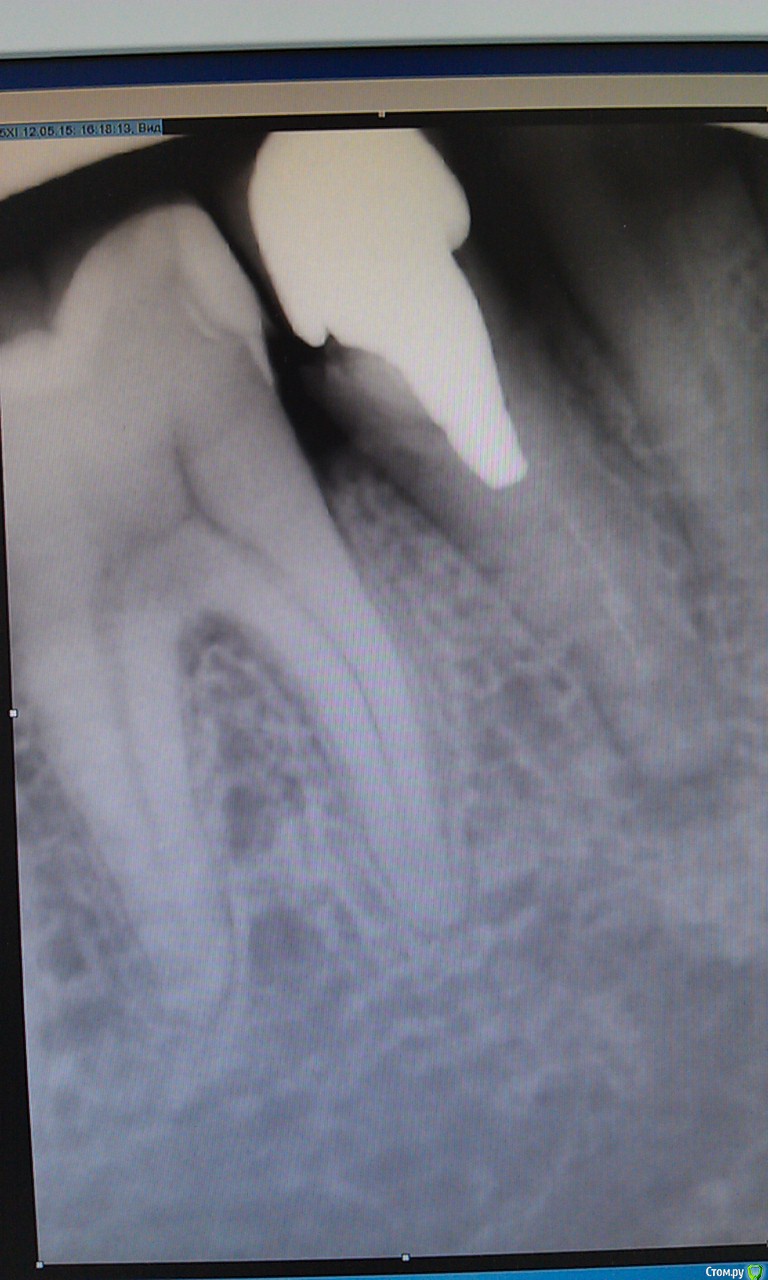

Валерия482 Опубликовано 12 мая, 2015 Поделиться Опубликовано 12 мая, 2015 Я человек очень далекий от стоматологии, по этому могу допускать ошибки в терминологии=)Ситуация:есть корень с культиевой вкладкой и коронкой на ней(металлокерамика), живу с этой конструкцией около 12 лет. 08.05.15 десна у корня отекла, появилась чувствительность зуба при прикусывании.10.05.15 появилась небольшая подвижность зуба, отек десны уменьшился.1 стоматолог (08.05) изучив снимок (на руках отсутствует) порекомендовал: удалить коронку, высверлить вкладку (успех 50 х 50), пролечить периодантит и далее в обратном порядке.2 стоматолог (12.05) изучив снимок (фото снимка прилагаются) вынес вердикт "удалять".Я на распутье, т.к. не могу решить что же делать.Помогите пожалуйста советом.Спасибо! Ссылка на комментарий

Гарриевич Опубликовано 13 мая, 2015 Поделиться Опубликовано 13 мая, 2015 + за перелечиваниевкладка короткая, извлечь ее будет достаточно просто Ссылка на комментарий